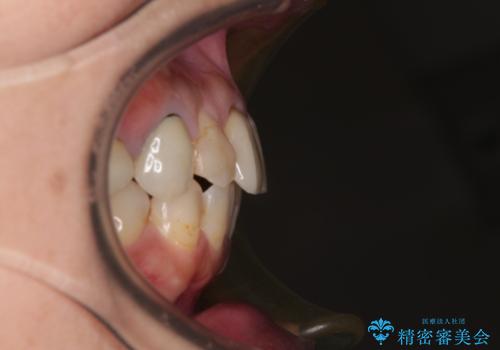

- 上下前歯のデコボコを気にして来院された患者様です。

歯列としては、ワイヤー装置でもインビザラインでも、どちらでも対応可能でしたが、処置されている歯が多く、ワイヤー装置を装着するためには処置歯のやり直しが必要な状態でした。

インビザラインでもアタッチメントを装着できないという同様のデメリットがありますが、比較的矯正治療を行いやすい歯列であったので、インビザラインによる矯正治療を行うこととしました。